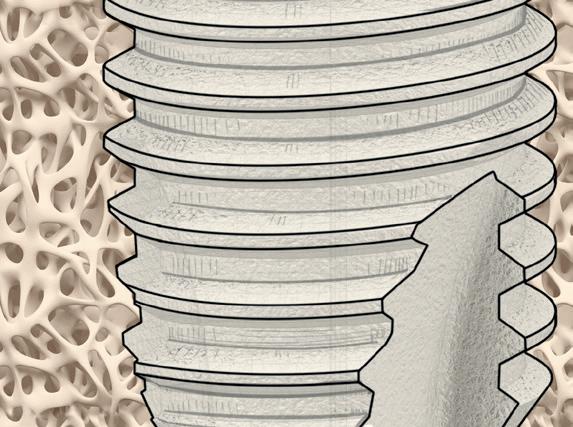

Elektrolytische Reinigung von Zahnimplantaten

Periimplantäre Erkrankungen betreffen immer mehr Patient*innen, da die Zahl der gesetzten Implantate weltweit exponentiell zunimmt.(1) Aus diesem Grund ist in den letzten Jahren auch die Behandlung von biologischen Komplikationen und vor allem die Behandlung einer Periimplantitis stärker in den Fokus gerückt.

Ein wesentlicher, jedoch schwieriger Schritt dabei ist die gründliche Reinigung der Implantatoberfläche. Unter den bisher in der Literatur beschriebenen Methoden im Rahmen der nicht-chirurgischen und chirurgischen Dekontamination erwies sich keine als eindeutig überlegen. (2,3)

Eine mögliche Lösung könnte das 2021 eingeführte Reinigungssystem GalvoSurge® bieten. Bei diesem Verfahren werden Zahnimplantate elektrochemisch dekontaminiert, indem das Implantat mit einer speziellen Reinigungsflüssigkeit besprüht und eine elektrische Kleinstspannung angelegt wird.

Als Folge fließt zwischen dem Sprühkopf (Anode) und dem Implantat (Kathode) Strom und das Wasser in der Elektrolytflüssigkeit (Hydroxy Carbonsäure, Natriumsalz, destilliertes Wasser) wird in Wasserstoff Kationen (H+) und Hydroxid Anionen (OH-) aufgespalten. Die dadurch entstandenen Wasserstoffbläschen sollen den Biofilm aufbrechen und ihn von der Implantatoberfläche ablösen (Abb. 1c).(4, 5) Dieses Verfahren dauert ca. 2 Minuten pro Implantat und ist mit den meisten Implantatsystemen kompatibel.

Aufgrund des jetzigen Sprühkopfdesigns beschränkt sich die Anwendung von GalvoSurge® jedoch auf verschraubte Suprakonstruktionen. Diese müssen vor der elektrolytischen Dekontamination abgenommen werden, damit eine sichere Verbindung zwischen dem GalvoSurge® Sprühkopf und der Implantatinnenverbindung hergestellt werden kann (Abb. 1a,b).

Abbildung 1. Der Sprühkopf (a) wird intraoperativ nach Abnahme der Suprakonstruktion (b) aufgesetzt und die während des Reinigungsprozesses entstehenden Wasserstoffbläschen sollen den Biofilm aufbrechen (c). Fotos © Kristina Bertl

Nach dem Abschrauben der Restauration muss ein Lappen abgehoben werden, um das periimplantäre Entzündungsgewebe gründlich entfernen zu können, da die reinigende Wirkung von GalvoSurge® sich nur da entfalten kann, wo die Spüllösung Kontakt zur Implantatoberfläche hat.

Anschließend kann der operative Eingriff je nach Defektkonfiguration fortgesetzt werden – resektiv oder rekonstruktiv; mehr dazu gab es bereits in unserem letzten Telegramm YOUNGSTERS TELEGRAMM 01-2024!

Zusammengefasst erfordert dieses Implantatreinigungssystem zur Zeit einen verschraubten Zahnersatz in Kombination mit einem chirurgischen Eingriff, was doch zahlreiche Periimplantitisfälle ausschließt. Daher wäre sowohl ein modifiziertes Sprühkopfdesign für zementierte Suprakonstruktionen als auch der Einsatz der elektrolytischen Reinigung im Rahmen einer nicht-chirurgischen Therapie interessant. Das Gleiche gilt für unabhängige klinische Studien, die die Wirkung dieses neuen Verfahrens weiter untersuchen, da die aktuelle Studienlage auf diesem Gebiet noch einige Fragen offenlässt.